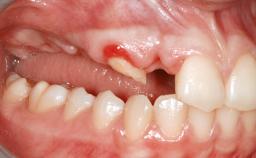

Iliac and Calvarial Bone Blocks for Onlay Grafting of a Severely Resorbed Edentulous Maxilla

A 45-year-old woman with a completely edentulous maxilla was referred to evaluate the possibility of rehabilitation with an implant-supported prosthesis. This patient was healthy and a non-smoker. She had been wearing a maxillary complete denture opposing a natural mandibular dentition since her twenties. This situation had resulted in progressive resorption of the alveolar ridge, repeatedly creating a need for relining the denture. Twenty years later, despite multiple adaptations and the use of “glues” the denture was unstable and causing the patient psychological and functional discomfort.

Bone Augmentation Horizontal|Sinus Floor Elevation|Staged|Vertical

Augmentation Materials Autogenous chips|Autogenous block(s)

Bone Volume Deficient vertically or deficient vertically AND horizontally